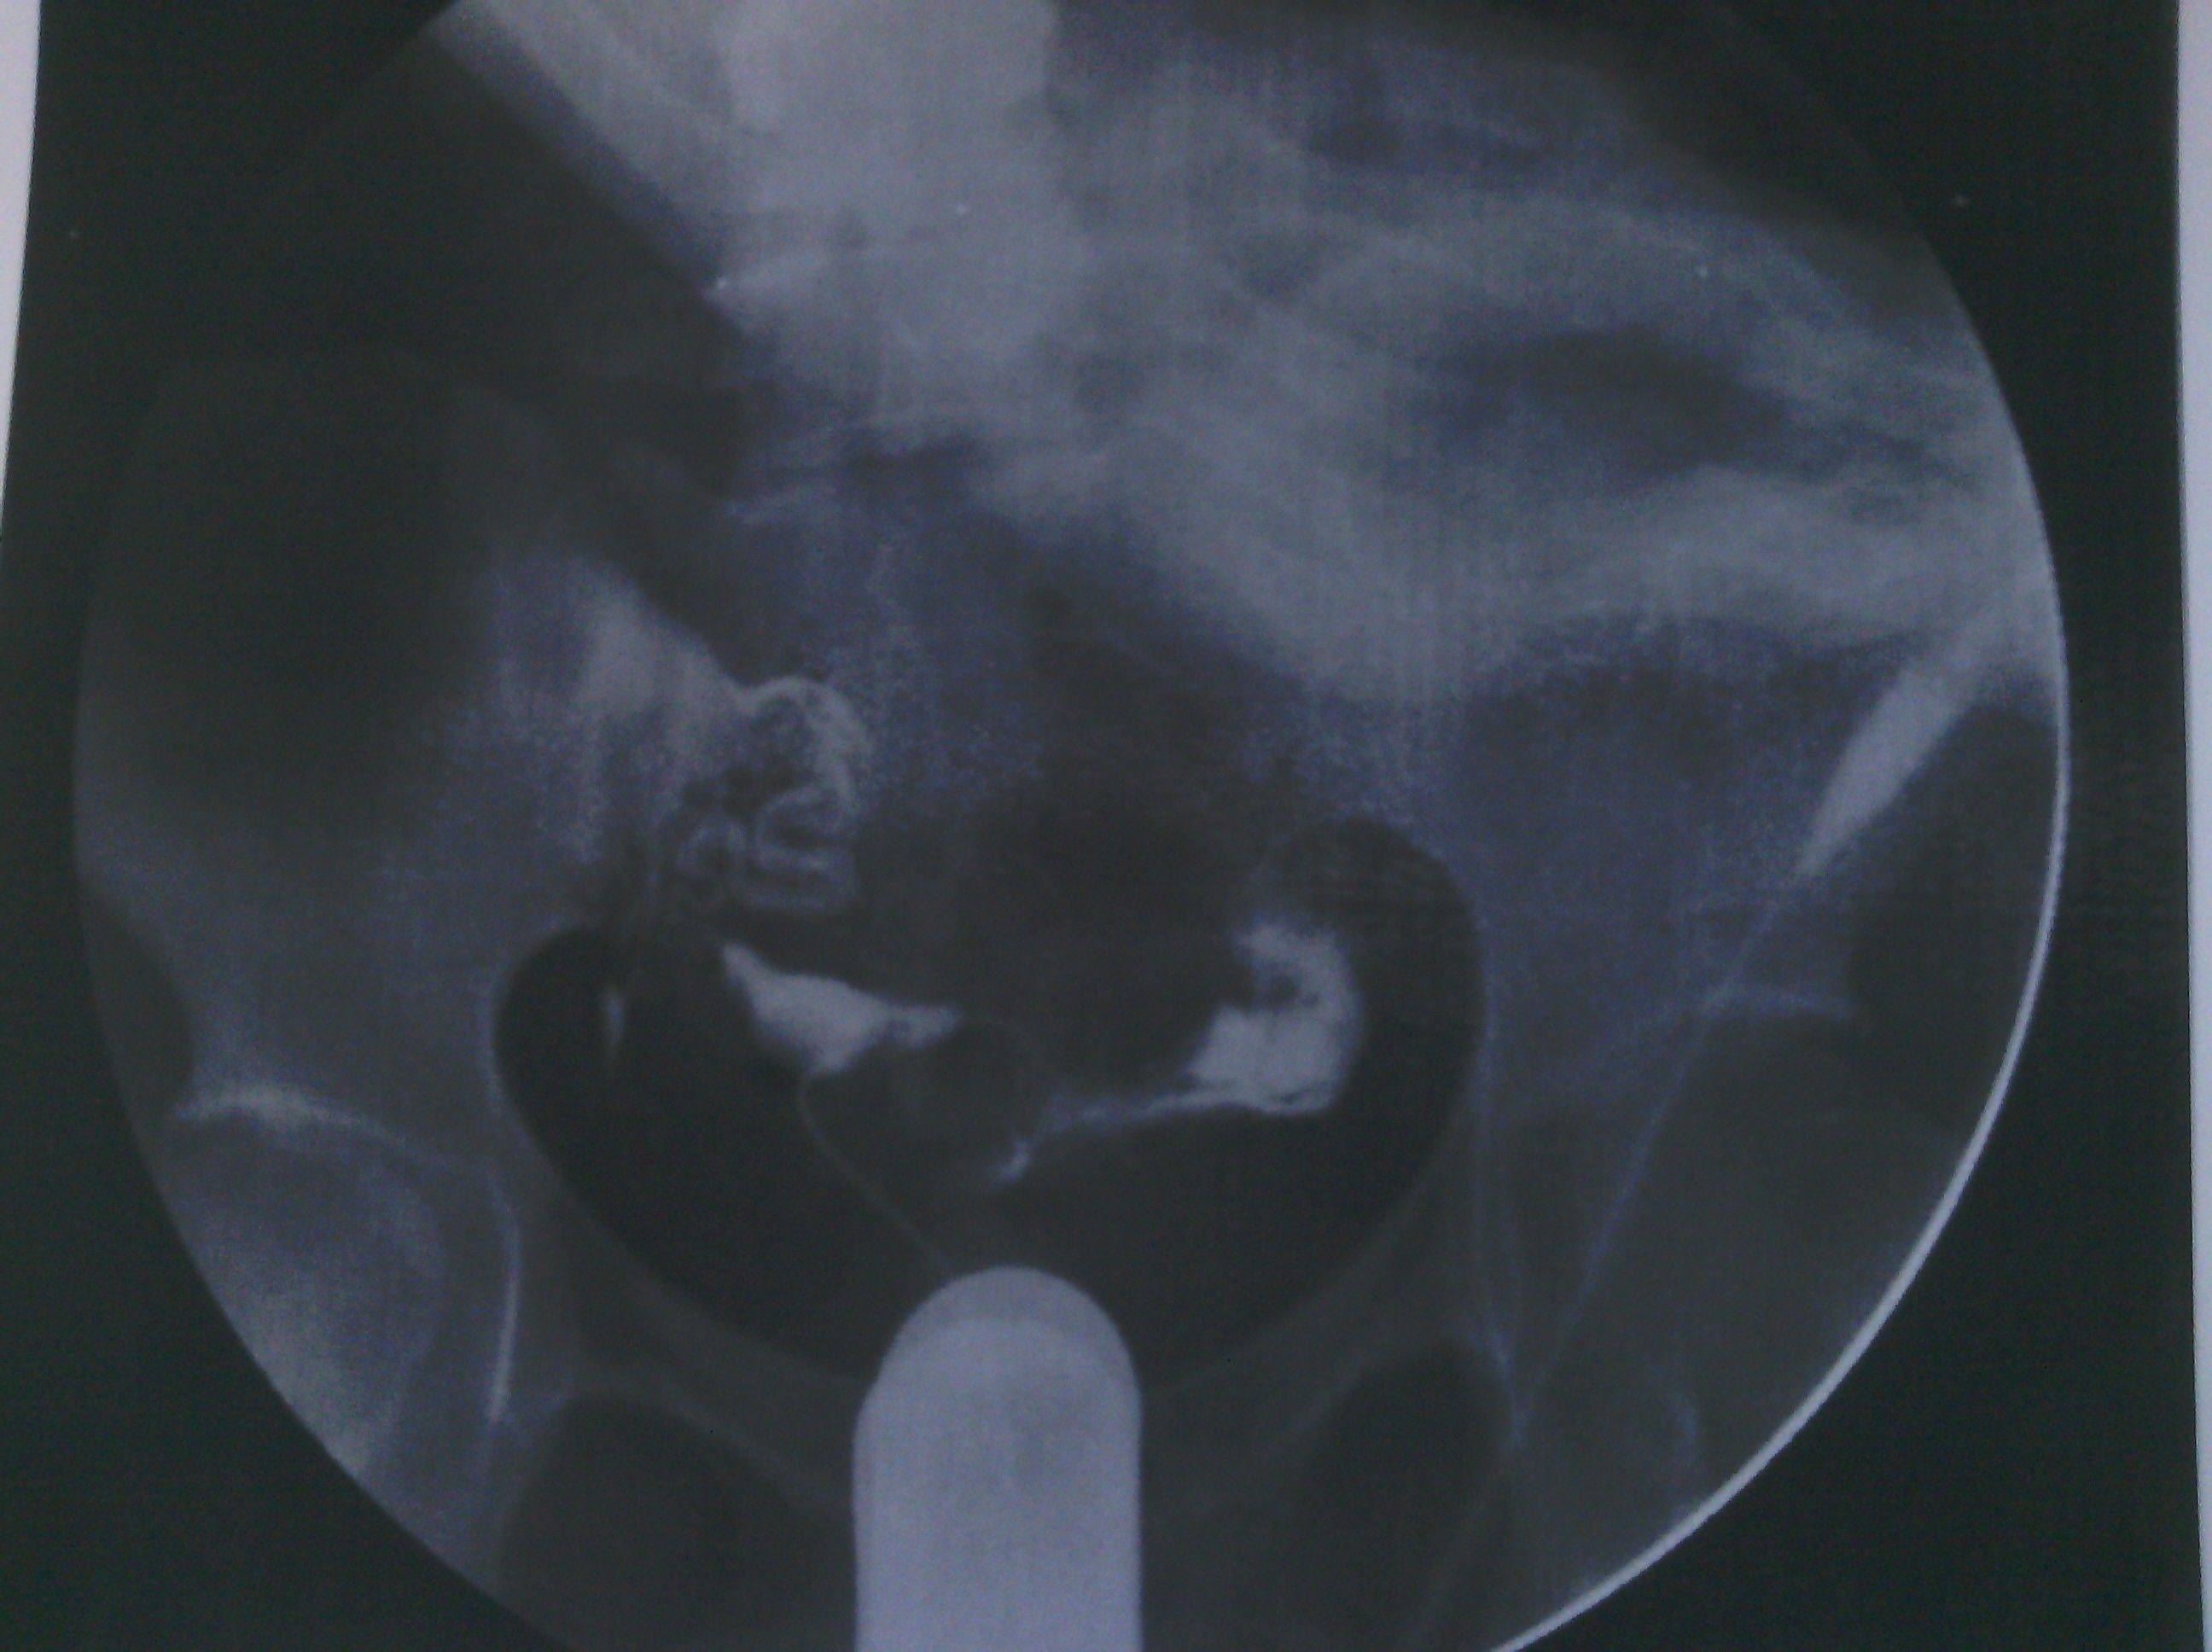

最新输卵管造影图片,麻烦各位大侠帮忙看看,纠结中 各位好,这是我11月6日做的输卵管造影图片,麻烦给看看现在是什么情况。在医院光说通而不畅有粘连,也没说哪个部位粘连,具体的是哪个部位有毛病呢?是间质部,峡部或是壶部。说少量弥散,然而弥散的片子也没延迟拍摄,是造影后直接就出来了,那判断的标准准确吗?看了好几年的病了,慕名到哪个医院去了,都没给过我合理化的建议,都是到哪家,哪家哪个拿手就推荐你做哪个,我现在看见医院两个字就想吐。我就是想,死,我也得死个明白。麻烦各位好心人看看我的片子给我一个合理化建议。现在的输卵管造影是个什么情况应该怎样治疗,在此拜谢各位了。我没啥财富值,对不起各位了。望能看片子解释一二,不胜感激。 点击展开 母婴用户710320885 2013-11-09 08:05 为您推荐: 其他回答 片子没标左右 所以我不清楚是哪边。 可以告诉你的是 面对我左边的输卵管走形上举,有黏连。面对右边的输卵管扭曲扩张。整个状况不是很乐观,具体治疗请咨询妇产科医生。 匿名用户 2013-11-11 14:28 相关问题 求讲解输卵管造影图片 妇科医生专家好:请帮忙看看这份“子宫输卵管造影检查报告”: 帮忙看看造影的报告,双侧输卵管炎不能怀孕了吗?

各位好,这是我11月6日做的输卵管造影图片,麻烦给看看现在是什么情况。在医院光说通而不畅有粘连,也没说哪个部位粘连,具体的是哪个部位有毛病呢?是间质部,峡部或是壶部。说少量弥散,然而弥散的片子也没延迟拍摄,是造影后直接就出来了,那判断的标准准确吗?看了好几年的病了,慕名到哪个医院去了,都没给过我合理化的建议,都是到哪家,哪家哪个拿手就推荐你做哪个,我现在看见医院两个字就想吐。我就是想,死,我也得死个明白。麻烦各位好心人看看我的片子给我一个合理化建议。现在的输卵管造影是个什么情况应该怎样治疗,在此拜谢各位了。我没啥财富值,对不起各位了。望能看片子解释一二,不胜感激。